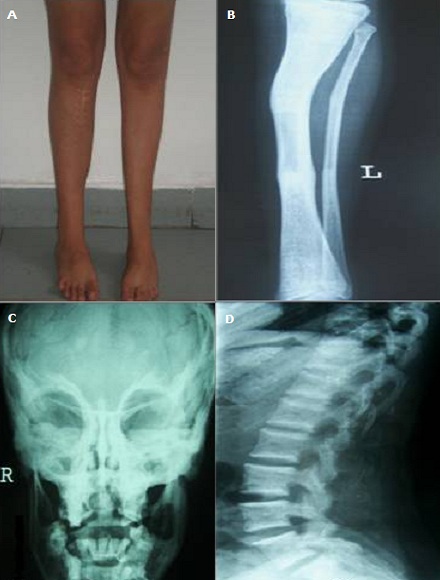

Patiente âgée de 21 ans adressée pour des abcès dentaires récidivants et victime depuis l'âge de six ans de multiples fractures des os des 4 membres. Elle a 2 frères ayant fait chacun des fractures osseuses multiples. Elle avait un retard staturo-pondéral et des déformations des os des membres inférieurs (A). Son morphotype se caractérisait par un aspect triangulaire au visage. L'examen de la bouche retrouvait une issue de pus de la molaire inférieure gauche. Les bilans inflammatoire et phospho-calcique étaient normaux. Les radiographies des membres inférieurs avaient montré une déformation osseuse (B), des cals osseux et du matériel d'ostéosynthèse. Par ailleurs, on a retrouvé une ostéocondensation diffuse avec un aspect en « loup de carnaval » du massif facial (C) et de « vertèbres en sandwich » sur la radiographie du rachis lombaire de profil (D). La densitométrie osseuse avait montré un T-score élevé à + 3,9 DS au niveau lombaire. Le scanner du massif facial a conclut à une ostéomyélite mandibulaire chronique. Devant ce tableau clinico-radiologique, on a éliminé les maladies ostédystrophiques: l'ostéogenèse imparfaite, l'ostéoporose juvénile idiopathique, le syndrome Ostéoporose généralisée et pseudogliome et l'hypophosphatasie . Ainsi, le diagnostic d' « Ostéopétrose » dans sa forme autosomique dominante compliquée par une ostéomyélite mandibulaire a été retenu devant la densité osseuse augmentée et les descriptions radiologiques. Une double antibiothérapie a été instituée associée à un débridement de la nécrose osseuse et à des séances d'oxygénothérapie hyperbare. L'évolution est faite par une amélioration clinique avec un recul de 12 mois.